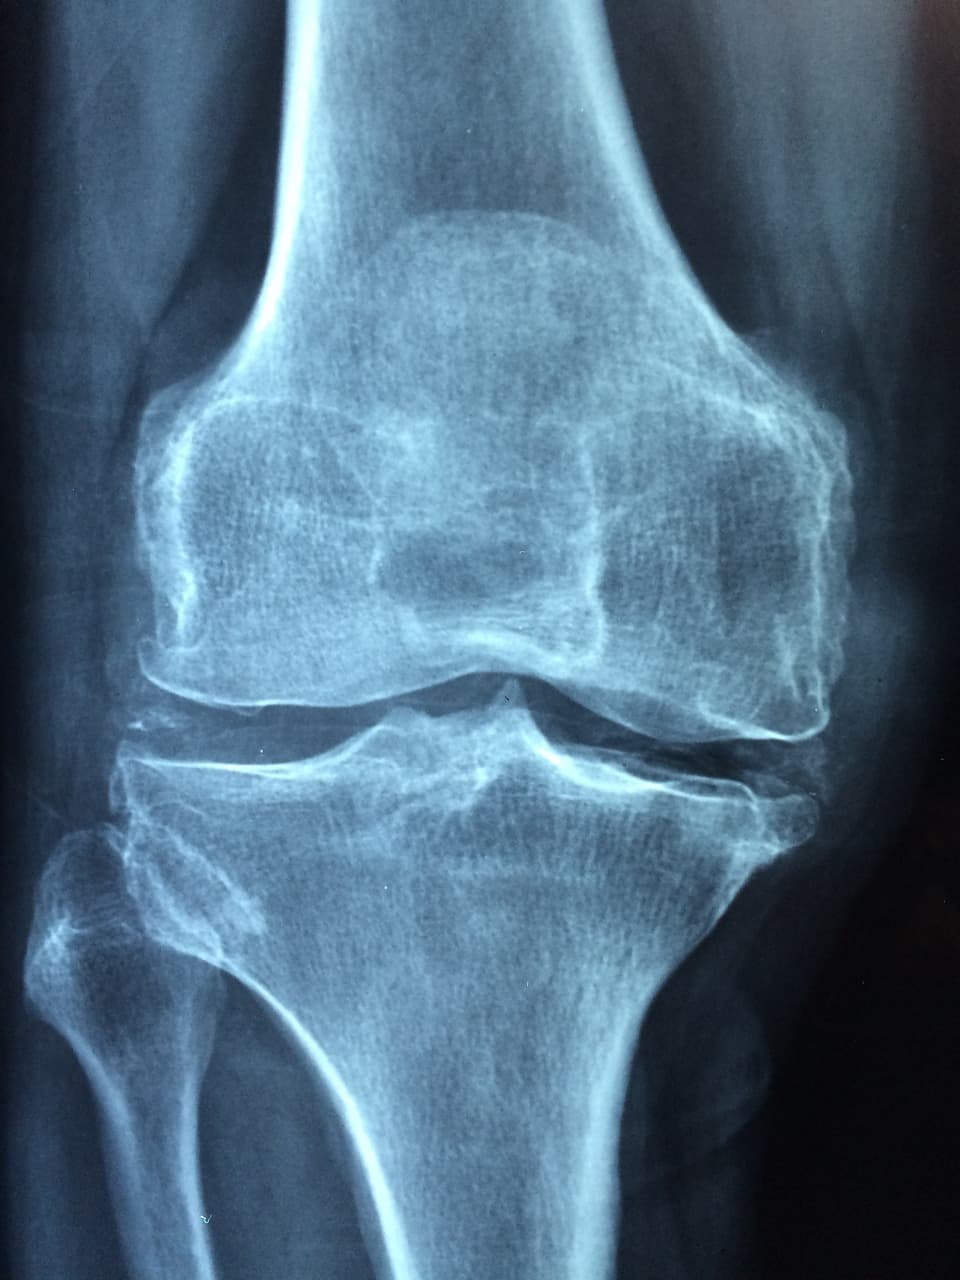

엑스레이 촬영에 이어 초음파 검사까지 받았고, 체외충격파 치료도 시행했다. 초음파 비용은 약 3만 원, 체외충격파는 6만 원, 진료비까지 합쳐 10만 원 이상이 들었다. 생각보다 큰 비용이 들어 놀라기도 했다.

연골연화증은 무릎을 구성하는 연골, 특히 슬개골(무릎뼈) 뒷면의 연골이 부드러워지고 마모되면서 통증과 기능 저하를 일으키는 질환이다. 슬개골 연골이 손상되면 관절을 움직일 때 마찰이 생기며, 통증, 뻣뻣함, 계단 오르내릴 때의 불편감 등이 나타날 수 있다.